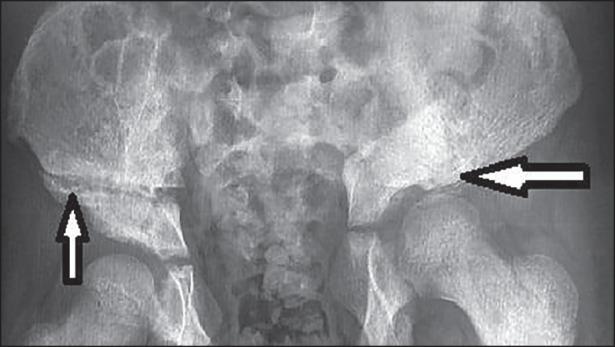

Out of four patients who underwent bladder exstrophy surgical management, aesthetic, functional outcomes and complications in the short and long follow-up were achieved in three patients. The first patient is a male and had a good penis aspect. He has a normal erection during micturition with a good jet miction. He has a moderate urinary incontinence, which requires diaper. In the erection, his penis-measures 4 cm long and 3 cm as circumference. The second patient was a female. She had an unsightly appearance of the female external genitalia with bipartite clitoris. Urinary continence could not be assessed; she did not have the age of cleanness yet. The third patient had a significant urinary leakage due to the failure of the epispadias repair. He has a limp, a pelvic obliquity, varus and internal rotation of the femoral head. He has an inequality of limbs length. Pelvis radiograph shows the right osteotomy through the ilium bone, the left osteotomy through the hip joint at the acetabular roof.

在接受膀胱外翻手术治疗的4例患者中,3例在短期和长期随访中获得了美学、功能效果及并发症方面的良好结果。首例患者为男性,阴茎外观良好。排尿时勃起正常,尿流良好。他有中度尿失禁,需要使用尿布。勃起时,他的阴茎长4厘米,周长3厘米。第二例患者为女性。她的女性外生殖器外观不佳,阴蒂二分。无法评估尿失禁情况;她尚未达到能自主保持清洁的年龄。第三例患者因尿道上裂修复失败出现大量尿漏。他有跛行、骨盆倾斜度、股骨头内翻和内旋。他存在肢体长度不等。骨盆X线片显示右侧通过髂骨截骨,左侧通过髋臼顶髋关节截骨。